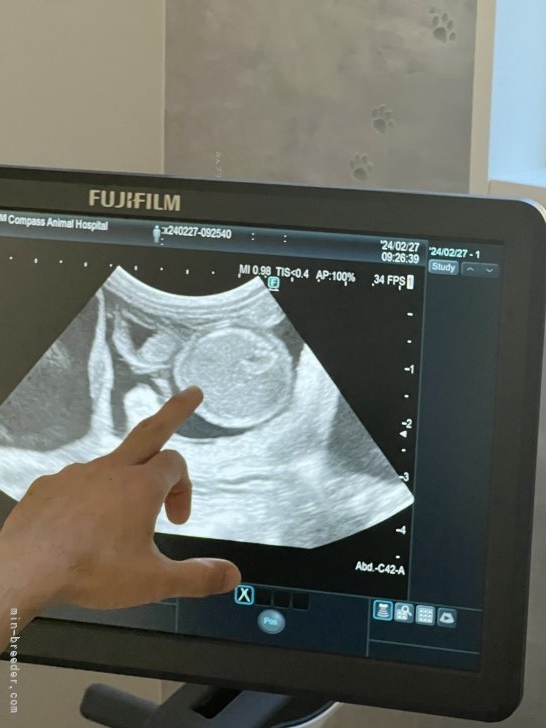

タルト当犬舎のJKC CH楓太と交配したタルト見事に妊娠しました。エコーけんさでは3匹入っていまし...